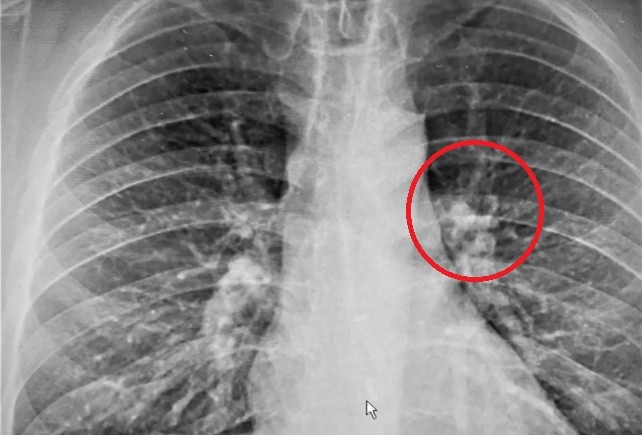

En un primer momento los médicos sugirieron un malestar relacionado con la comida. Para cerciorarse, le realizaron un chequeo que incluyó rayos X y entonces confirmaron la sospecha de la familia.

"Todos estaban boquiabiertos, mirando la radiografía en la pantalla, donde se podía ver con una definición muy clara", contó Gauthier, quien quedó con el auricular trabado en el esófago.